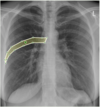

What is highlighted?

Lingula